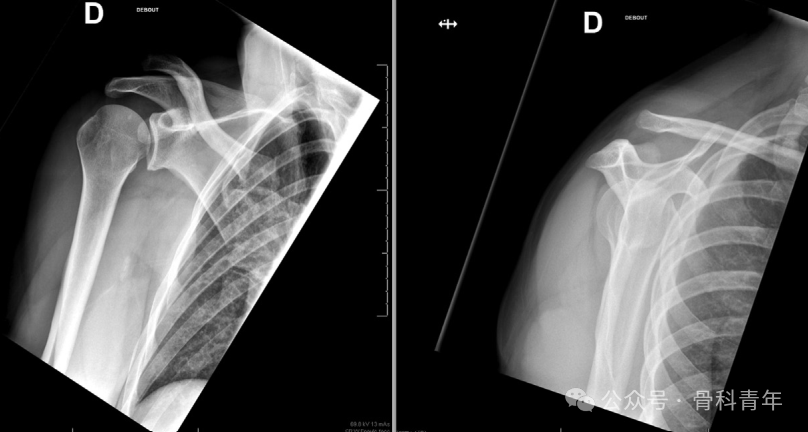

步骤7:肩锁关节复位与固定

骨剥压低锁骨,同时另一手以患肢为杠杆抬高肩部,实现肩锁关节临床复位。术者维持复位位置,助手逐步收紧双尾紧绳系统的缝线,无需严格打结,但为增强稳定性可进行缝合固定。术中通过透视检查确认复位效果,满意后剪断TigerWire(喙突侧)和白色缝线(锁骨侧),再打结并剪断蓝色缝线。

图片